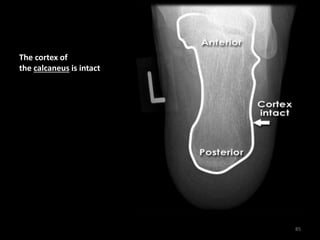

Normal calcaneus - Axial

84

The cortex of

the calcaneus is intact

85